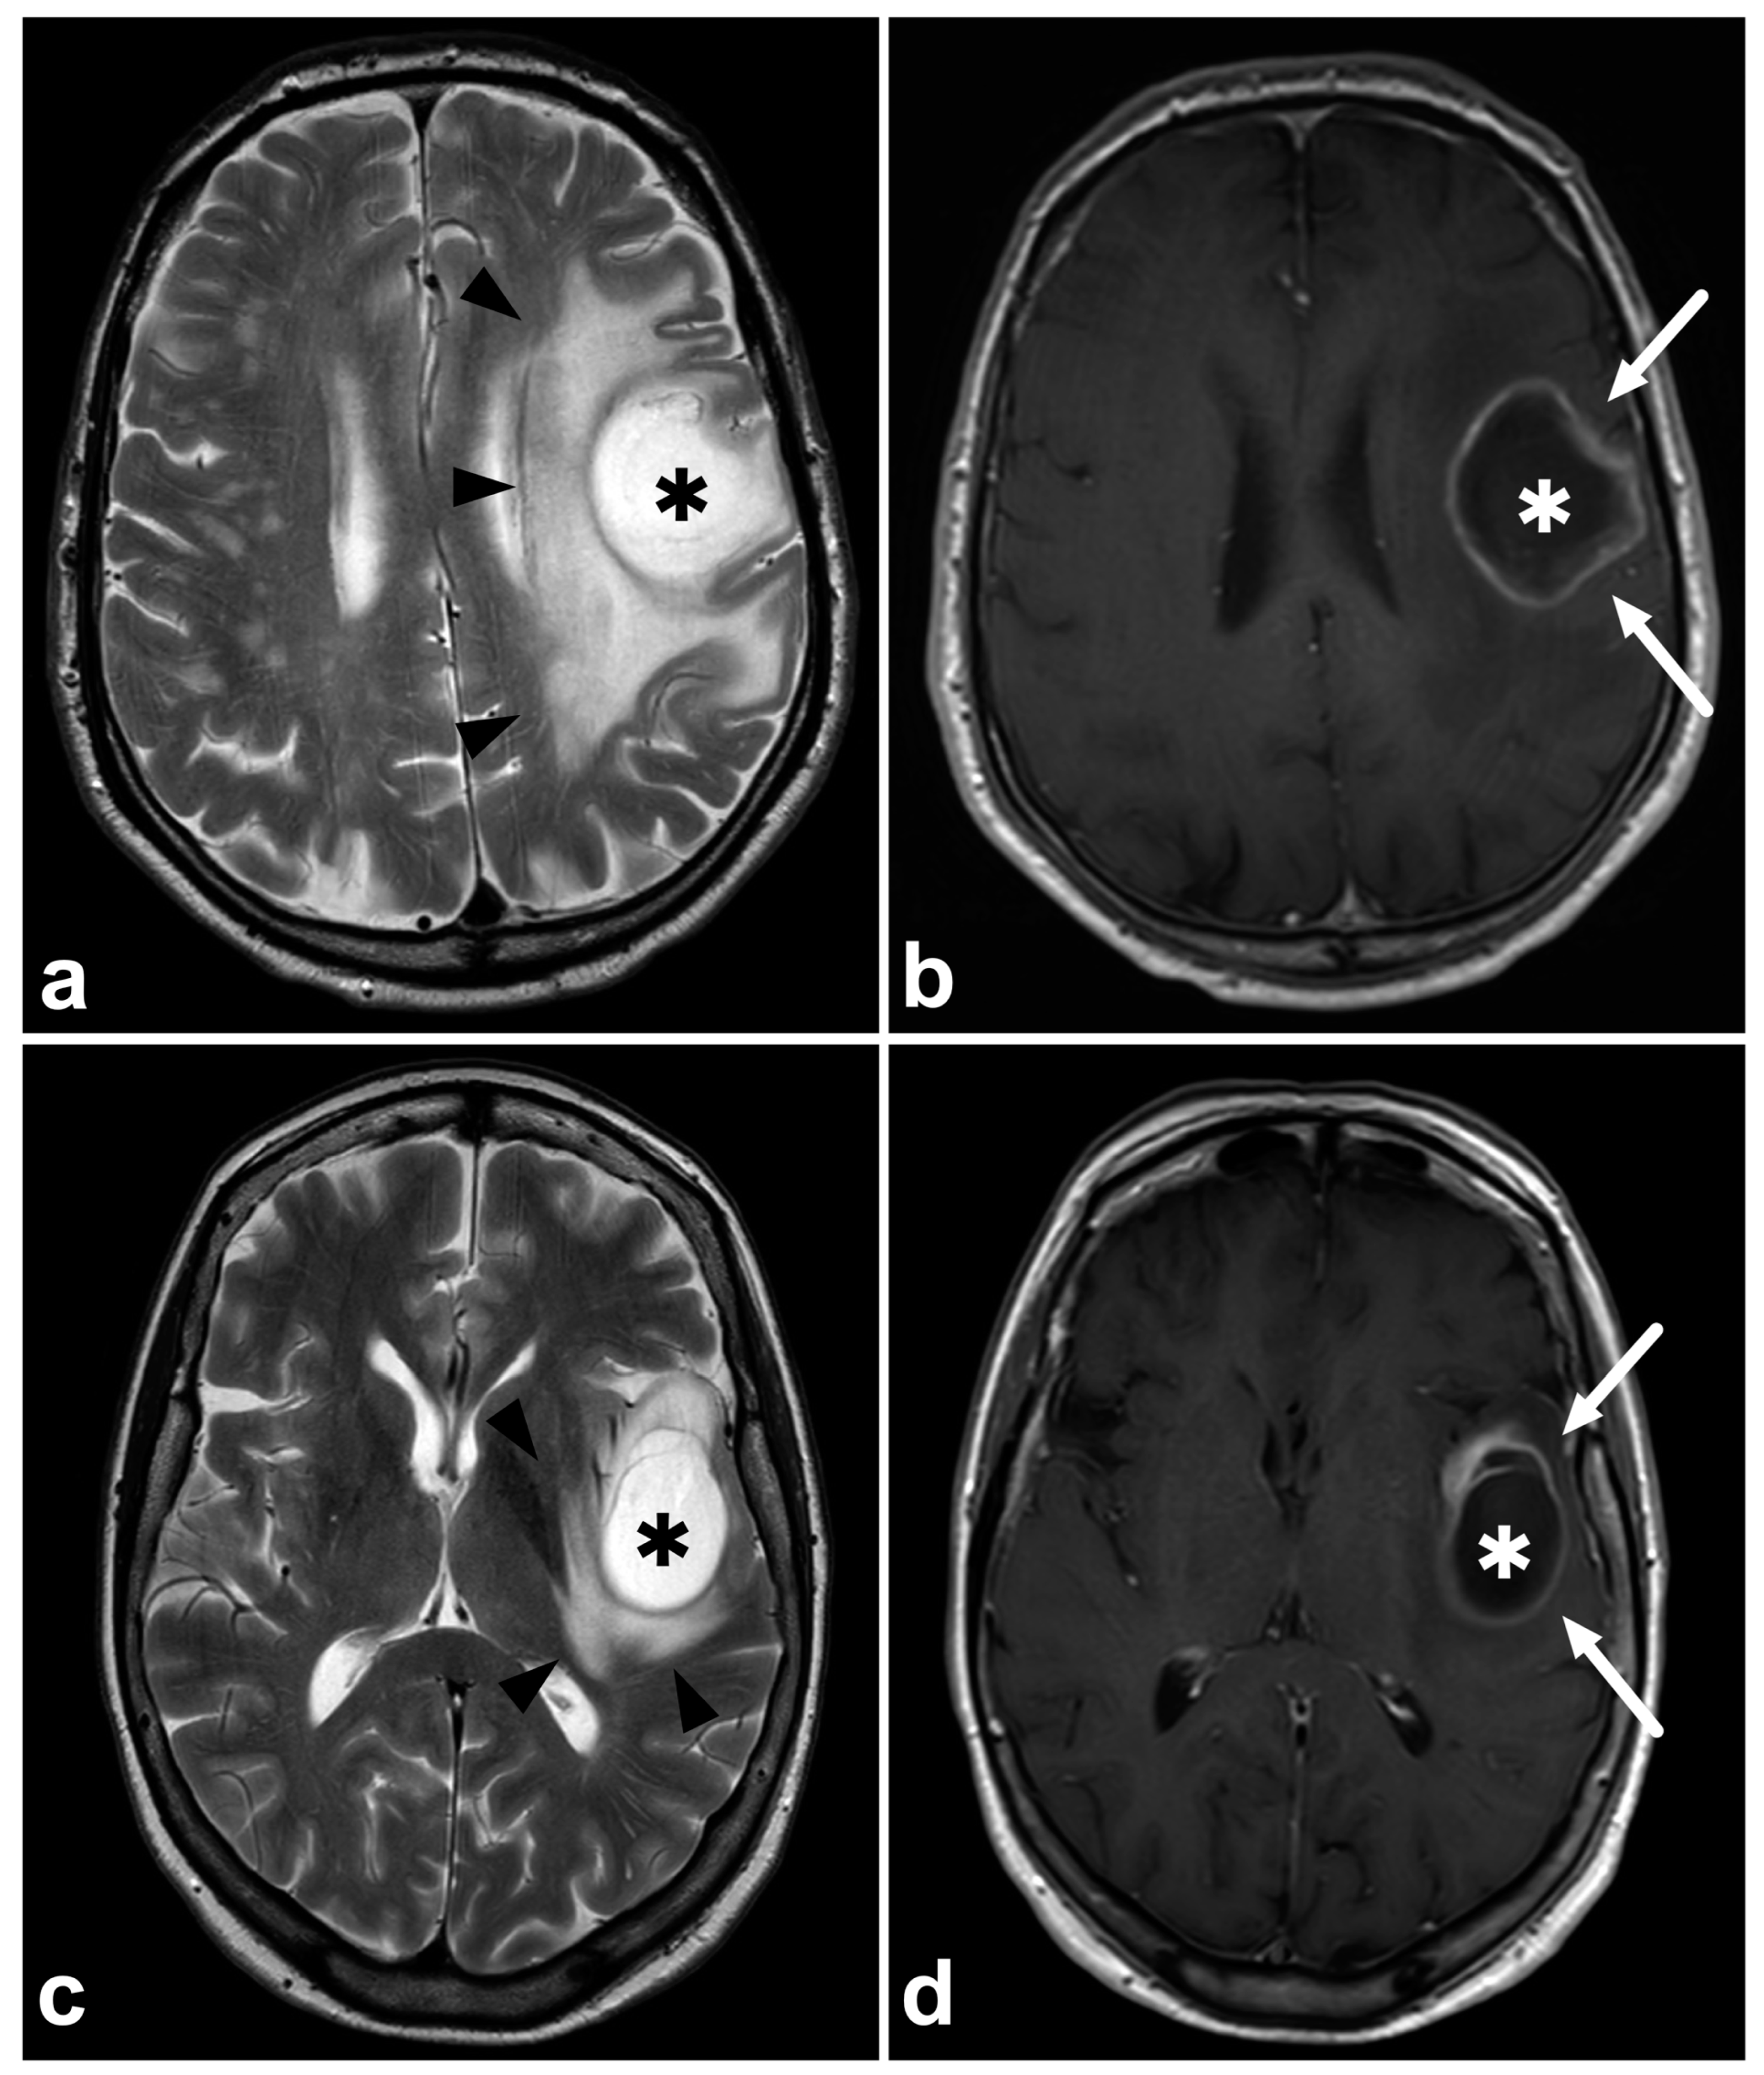

Correct tentative tumor type characterization reduces unnecessary steps in the definitive diagnostic pathway. A suspicion of metastasis or lymphoma should lead to a search for the primary tumor and determination of disease extent, while in gliomas, further imaging is not routinely needed. Figure 2 demonstrates two examples of glioblastomas, of which another one was initially suggested to represent a solitary metastasis. This led to unnecessary thoracoabdominal computed tomography to search for a primary tumor. Unnecessary scans mean increased expenses, radiation exposure, and delayed treatment. Regardless, knowing the difficulties in discriminating glioma from metastasis based on MRI only, the threshold for performing thoracoabdominal CT in case of newly detected brain tumors must remain low.

Figure 2.

(a) Patient 1, axial T2-weighted MRI, (b) Patient 1, axial gadolinium-enhanced T1-weighted spin-echo MRI, (c) Patient 2, axial T2-weighted MRI, (d) Patient 2, axial gadolinium-enhanced T1-weighted spin-echo MRI. Two patients with a histopathologically confirmed glioblastoma. Patient 1 (upper row) was initially suggested to have a solitary cerebral metastasis (asterisks), primarily because of the rapid appearance of the tumor (the previous MRI six months earlier was unremarkable) and because of the extensive edema surrounding the tumor (black arrowheads). Patient 1 underwent a thoracoabdominal CT scan to detect the primary tumor and other metastases. Patient 2 (lower row) was initially suggested of having a glioblastoma (asterisks) and the patient was immediately directed to the neurosurgeon without unnecessary steps. The diagnosis of glioblastoma was later confirmed histopathologically. Both tumors demonstrate a homogenous, probably necrotic center (asterisks) surrounded by a gadolinium-enhancing rim (white arrows). The enhancing rim is surrounded by a T2-hyperintense zone consisting of poorly delineated tumor infiltration and vasogenic edema, sometimes inseparable from each other with conventional clinical imaging. Brain metastasis often represents very similar MRI findings compared to glioblastomas.